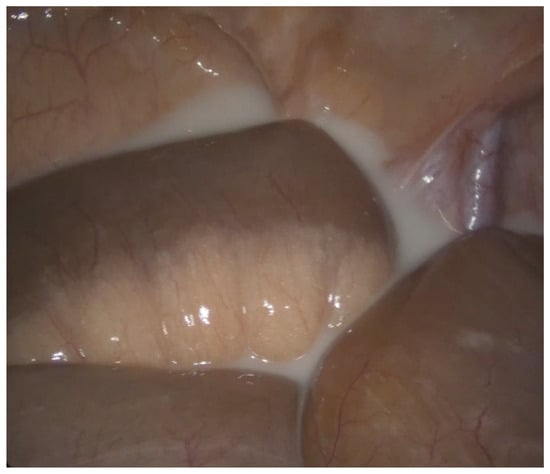

2.1.1. Case 1

2.1.2. Case 2